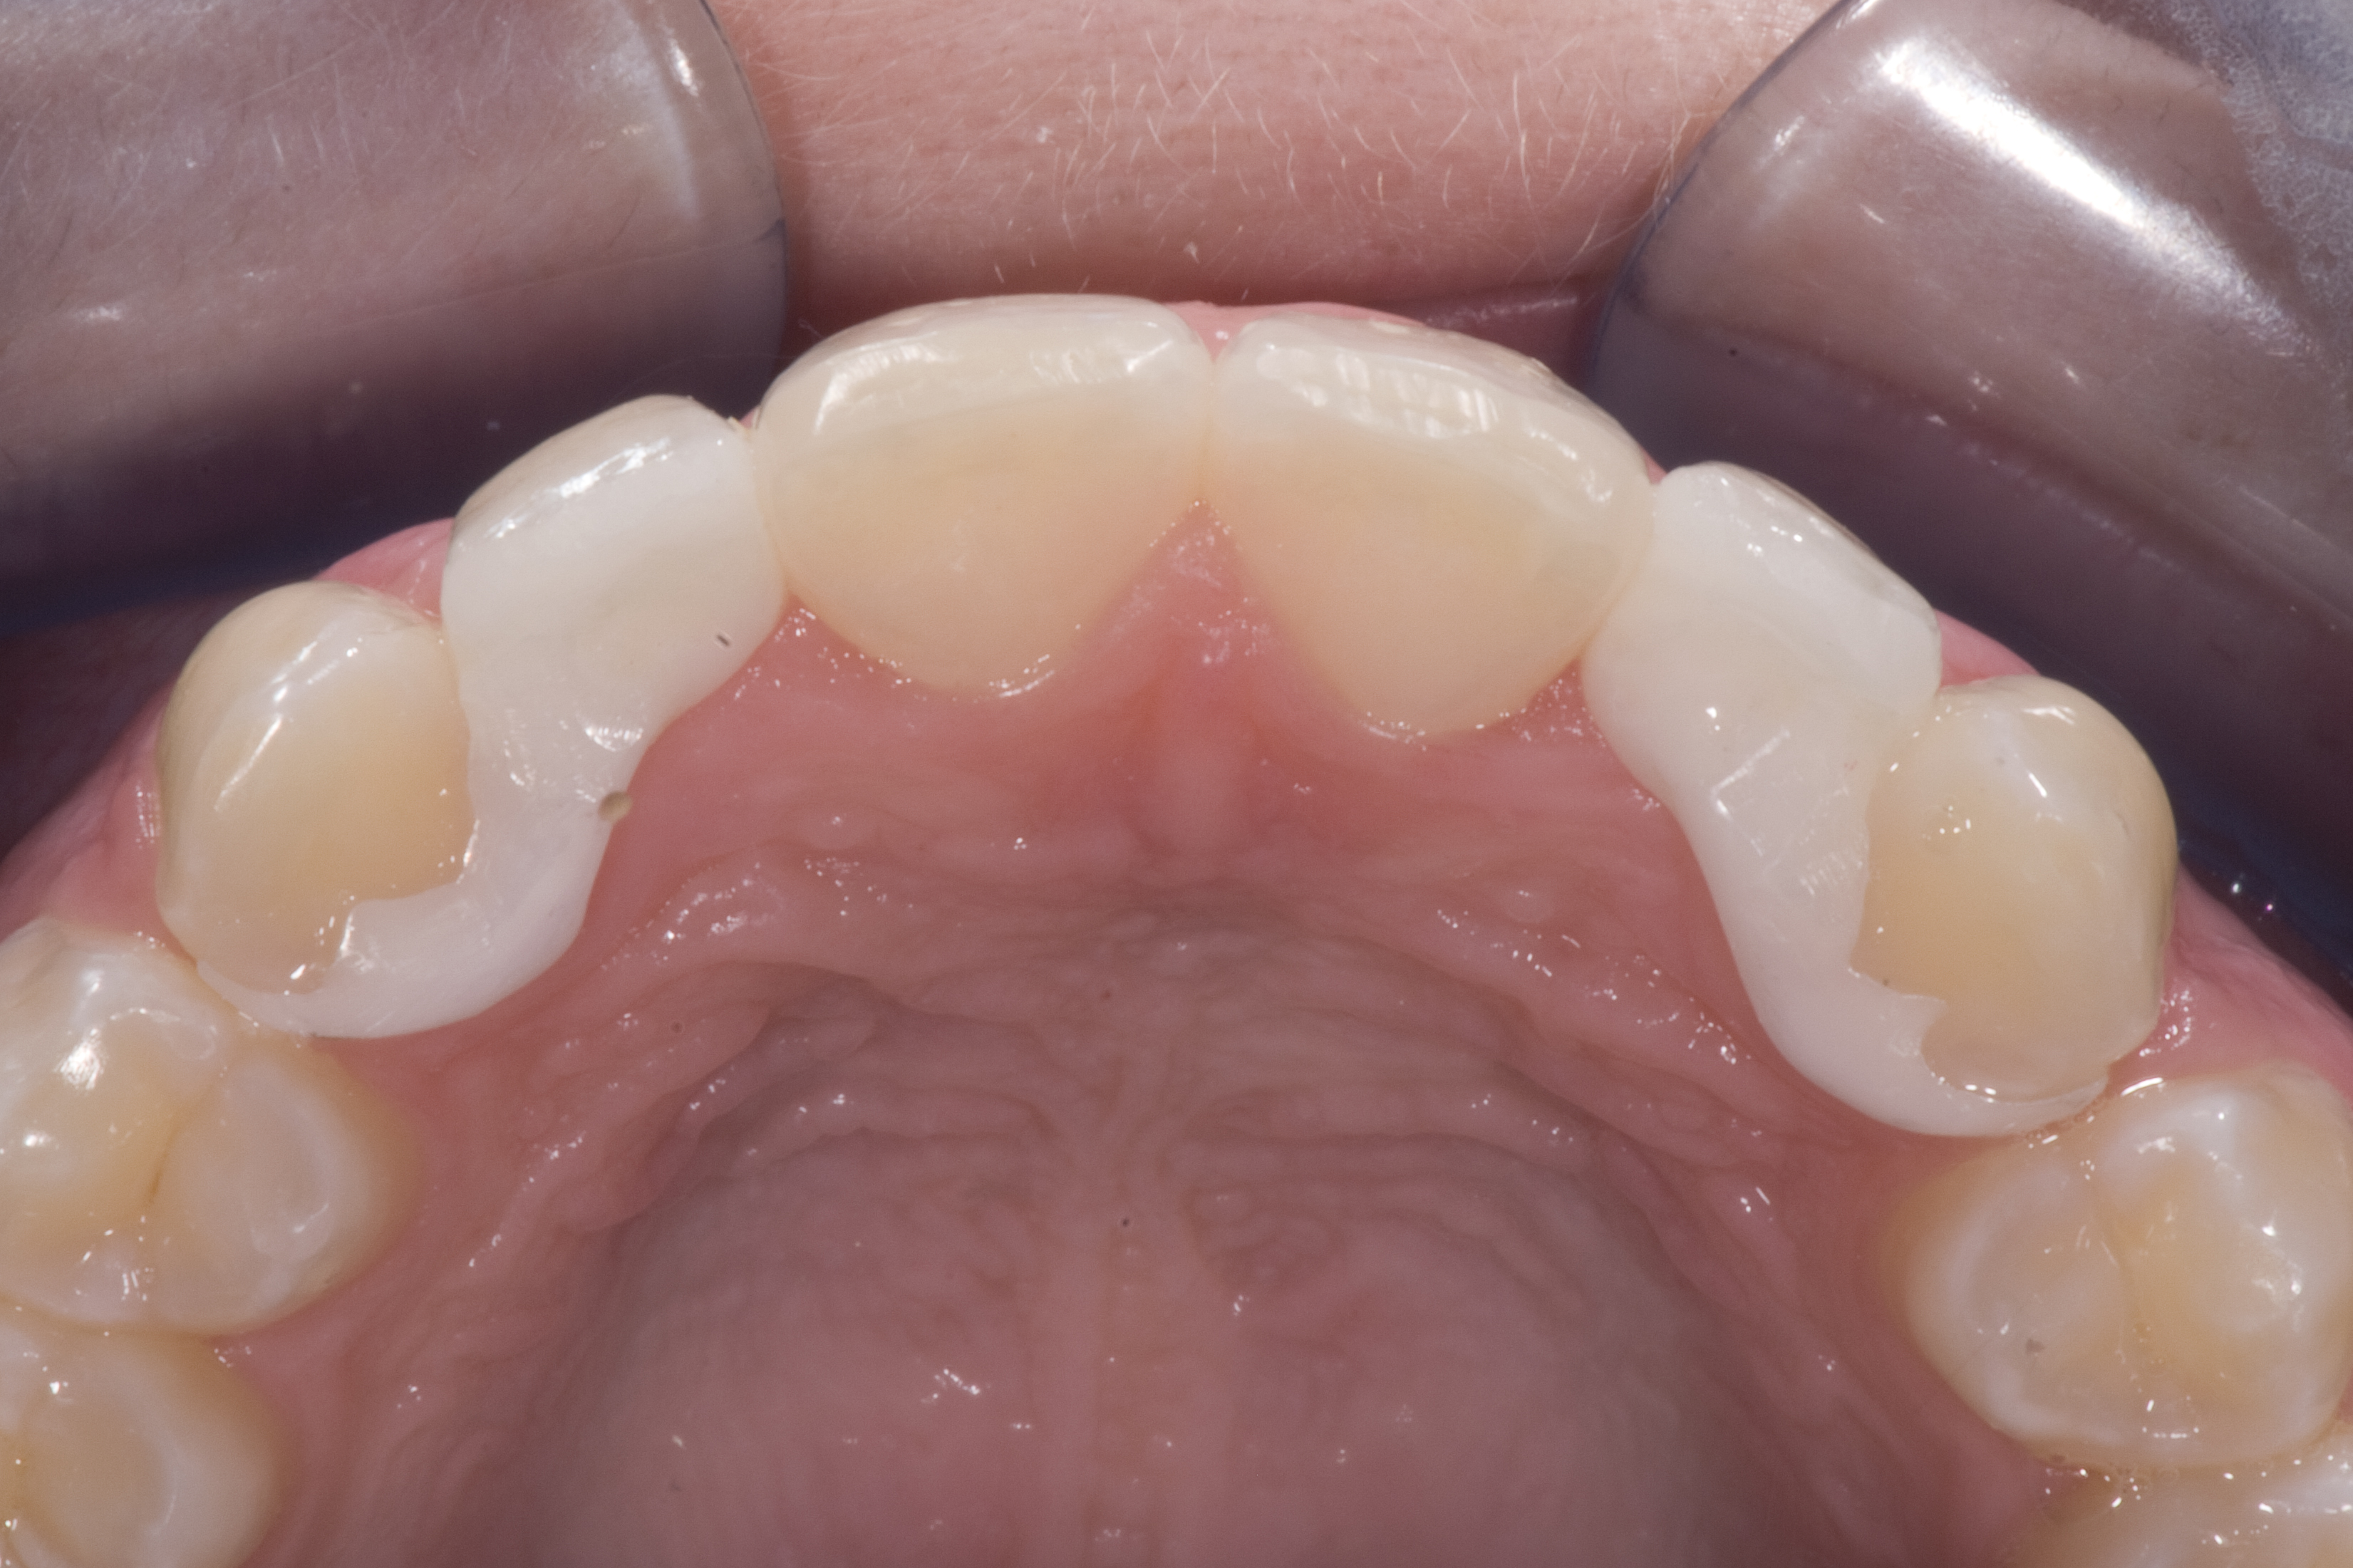

(12.) 15-year-old girl after orthodontic therapy idealized maxillary lateral incisor spaces.

Figure 12

(13.) Deficient ridges in the areas of the missing lateral incisors.

Figure 13

(14.) Occlusal view. Some form of augmentation would be needed if implants were being considered.

Figure 14

Some patients do not want an implant due to the need for surgical intervention, and others may not have enough space for implant placement. A 15-year-old patient presented to the office after completion of orthodontic treatment to idealize the spacing of her teeth and improve her occlusal relationship (Figure 12 through Figure 14). Because both of her maxillary lateral incisors were missing, the patient was wearing a retainer with lateral incisor pontics. She had a busy school schedule, but expressed her desire for a fixed restorative option. All of her options were discussed, and the patient was informed that if she wanted an implant, she would have to wait for at least 3 to 4 years for completion of growth. The patient was not sure if or when she wanted to have an implant placed in the future, especially considering her busy schedule and desire to attend college after high school. Considering her age and the need to be conservative, a single-wing zirconia Maryland Bridge was chosen as the ideal prosthetic replacement option. Because bonding a non-etchable and smooth surface such as zirconia requires chemical adhesion, it was decided to use a modified technique to make the bridge more retentive. One of the ways to improve adhesion of a zirconia bridge is to use an etchable feldspathic ceramic layer on the internal surface of the zirconia retainer.56-58 Unfortunately, it can be difficult to determine the thickness of the ceramic and ensure accurate seating of the restoration.